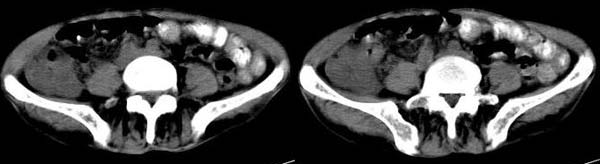

男 74岁,聋哑人,病史不详。

升结肠壁明显不规则增厚,呈偏心性,考虑结肠癌。

右半结肠不规则 弥漫性增厚,与周边胀器分界清楚,建议行钡剂灌肠.单纯本片还是考虑:升结肠癌.

[face=新宋体]1.结肠癌,2.回盲部炎变[/face]

1.结肠癌,2.回盲部炎变  [盲升结肠壁不均匀增厚,盲肠边缘模糊]

1.结肠癌,2.回盲部炎变